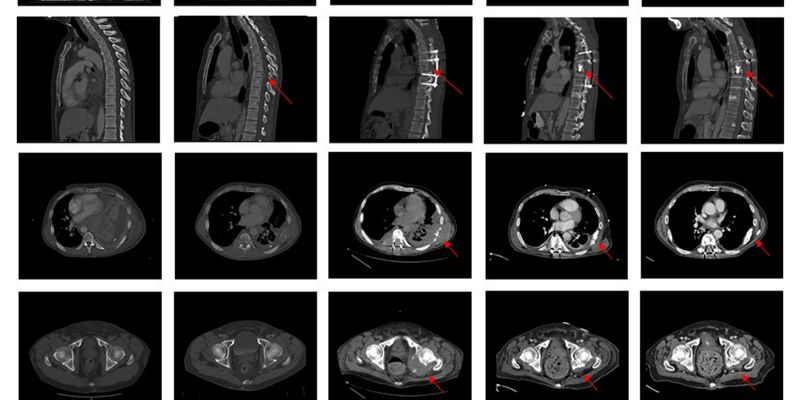

本文深入解析梅奥诊所如何通过多学科协作(MDT)成功治疗一例罕见、危及生命的甲状腺癌晚期病例。该肿瘤侵犯了患者的心脏和气道,治疗难度极高。了解复杂癌症的治疗挑战、MDT模式的优势以及国际顶尖医疗机构的集成护理能力,为患者寻求最佳治疗方案提供参考。 Read More... "罕见甲状腺癌侵犯心脏气道:梅奥诊所MDT团队如何成功挑战复杂手术与治疗方案"